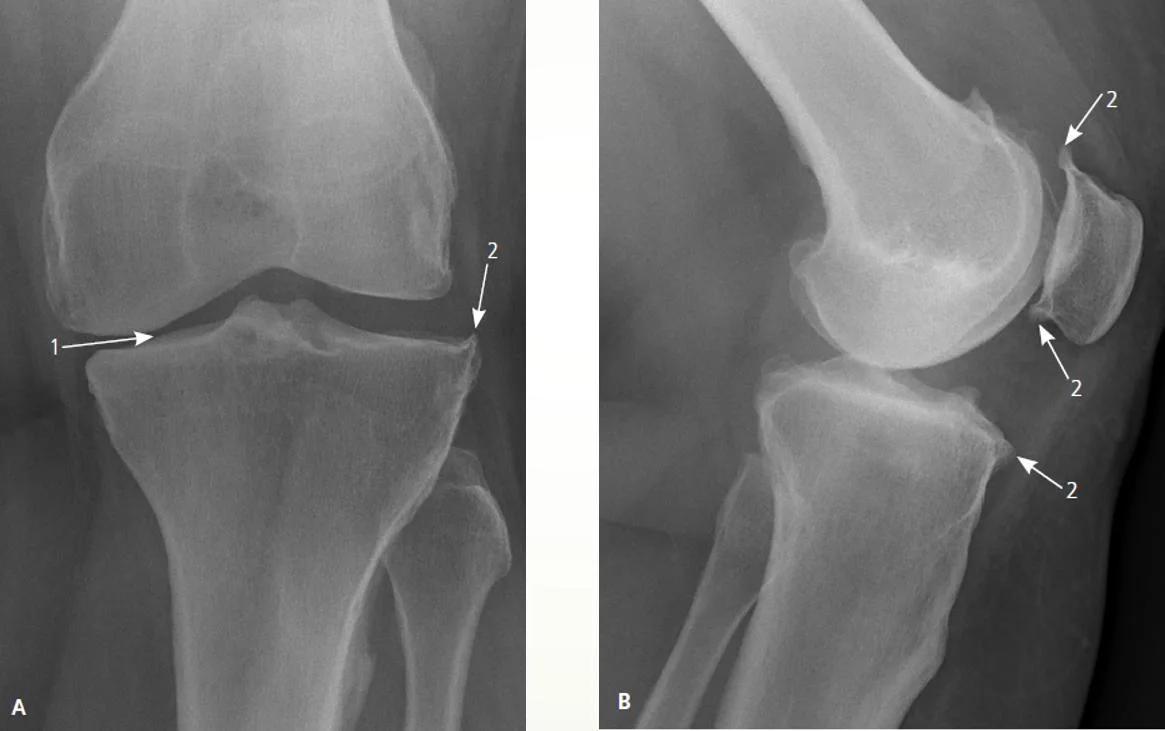

Plain X-ray of the knee for a 60-year-old lady with OA.

- Joint Space Narrowing: Usually asymmetric, often affecting the medial tibiofemoral compartment more than the lateral. 2. Osteophytes: Bony spurs forming at the joint margins (e.g., tibial spines, femoral condyles, patellar edges).

Other findings that may appear - Subchondral Sclerosis: Increased bone density in the bone immediately beneath the cartilage layer. - Subchondral Cysts: Fluid-filled cavities in the bone near the joint surface. - +/- Malalignment: Varus (bow-legged) or valgus (knock-kneed) deformity may develop.